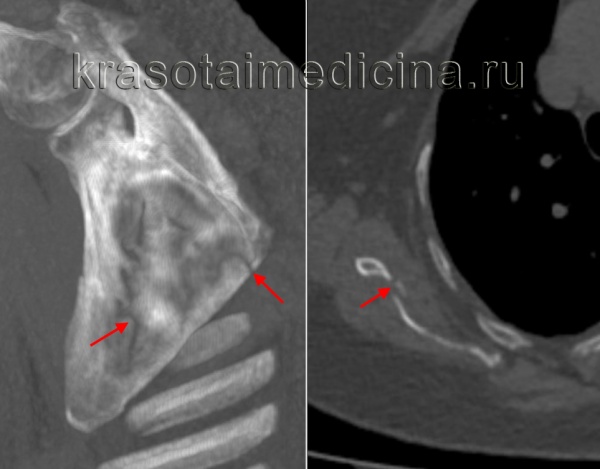

Наиболее точная информация о характере перелома может быть получена с помощью компьютерной томографии с пространственной реконструкцией.

Компьютернаятомограмма: перелом тела лопатки.

Компьютернаятомограмма: сложный многооскольчатый перелом тела лопатки

Компьютернаятомограмма: сложный многооскольчатый перелом тела лопатки и нижнего края суставной впадины лопатки